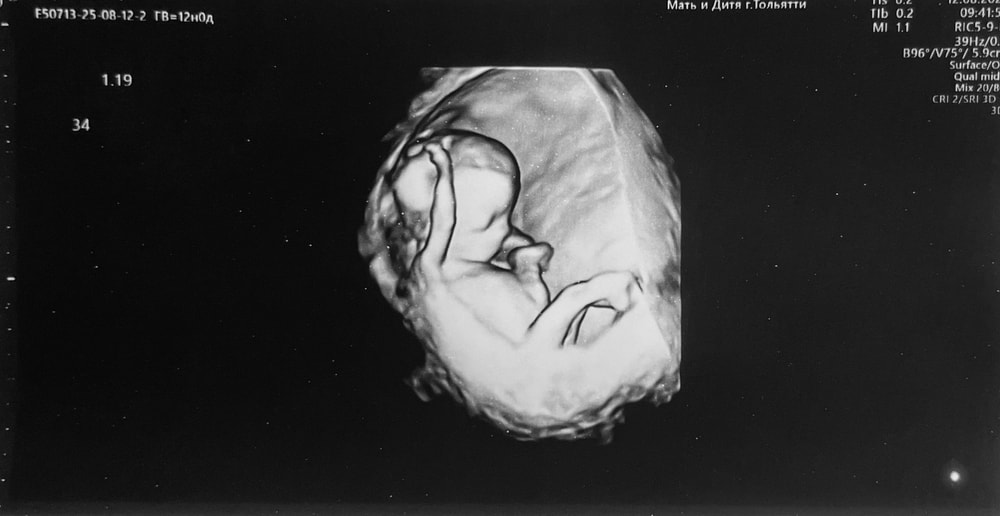

1 скрининг. 12 недель 🤰

Сегодня ровно 12 недель. По УЗИ все хорошо 🙏🏼 Жду результат анализа крови.

КТР 60

БПР 18

Длина бедра 7.7

ОГ 68

ОЖ 57

ТВП 1.6

Носовая кость визуализируется

ЧСС 153

Пульсационный индекс в венозном протоке 1.19

Левая маточная артерия 1.67 пи

Правая маточная артерия 1.82 пи

Шейка матки 34

Как здорово🥰 даже в 3д дали фотку сделать,или это 4д😅